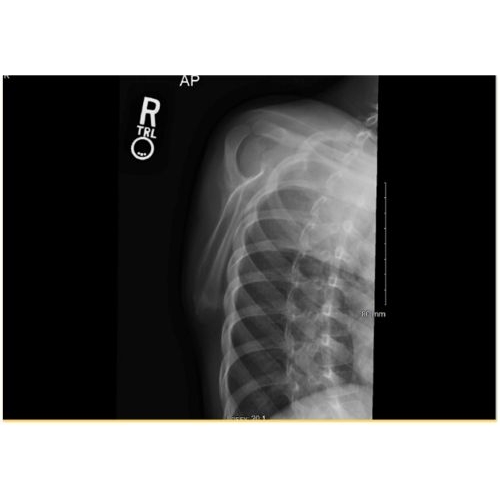

Physical examination and radiographic imaging results were consistent with an inferior angle scapular avulsion fracture.

At six weeks, the patient demonstrated full pain free range of motion, symmetric strength bilaterally, including scapular protraction, with no evidence of scapular winging. Repeat x-rays demonstrated bony callus formation at the fracture site, and evidence of resorption of the cartilage fragment Case Photo #7 , Case Photo #8 . Follow up was scheduled for 12 months to confirm appropriate bony healing.